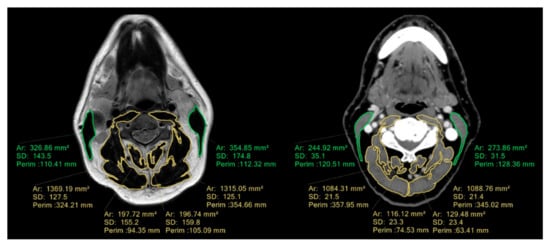

2.3. CT/MRI at C3 Level

- CT/MRI-defined cervical SMM: 34.91 cm2 (sensitivity 70%, specificity 64%, VPP 52%, VPN 79%; prevalence of low SMM: 48%, 31/65);

- CT/MRI-defined CSMI: 11.25 cm2/m2 (sensitivity 57%, specificity 69%, VPP 50%, VPN 74%; prevalence of low SMM: 40%, 26/65).